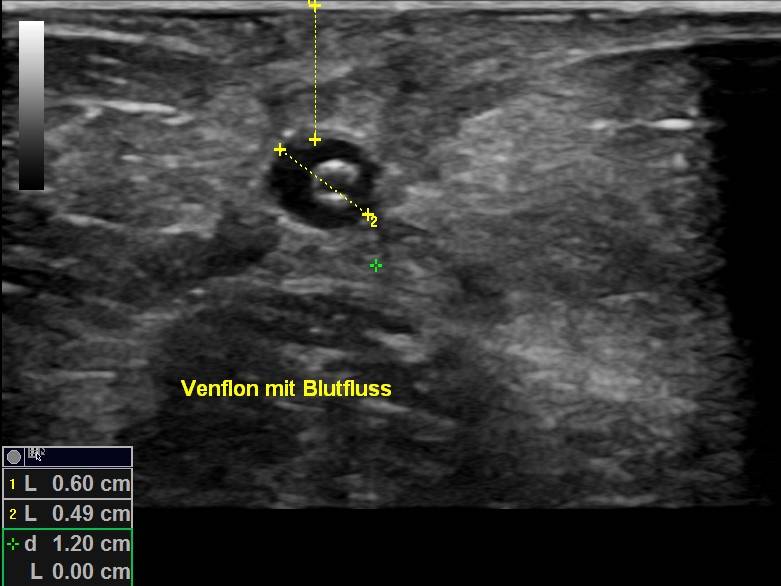

Spitz eines gelegten Dialysevenflons